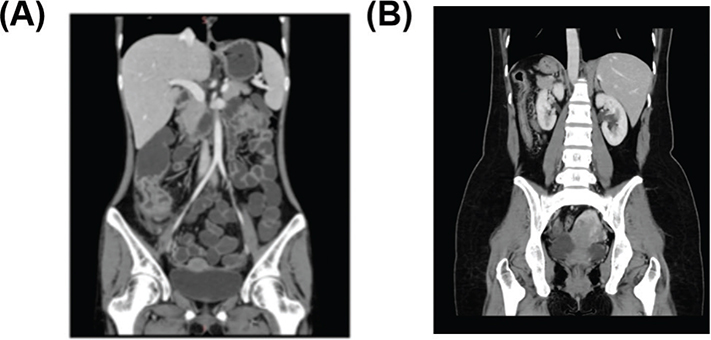

The typical imaging images observed in the two groups are provided in Figure 2. As could be seen from Figure 2a, patients with UC accompanied by dysplasia had typical imaging features such as pseudopolyps, intestinal stenosis, and bowel wall thickening. From Figure 2b, it could be observed that patients with UC without dysplasia had diffuse bowel wall thickening, mucosal enhancement, and absence of palatal folds, among others. The types and specific characteristics of CTE imagological examination in patients with dysplasia are shown in Table 3. Patients with dysplasia often presented with mesenteric lymphadenopathy, mucosal abnormal enhancement, and bowel wall thickening.

Figure 2

Figure 2. The CTE imaging image of dysplasia in patients with UC (a) and the CTE imaging image of non-dysplasia in patients with UC (b).